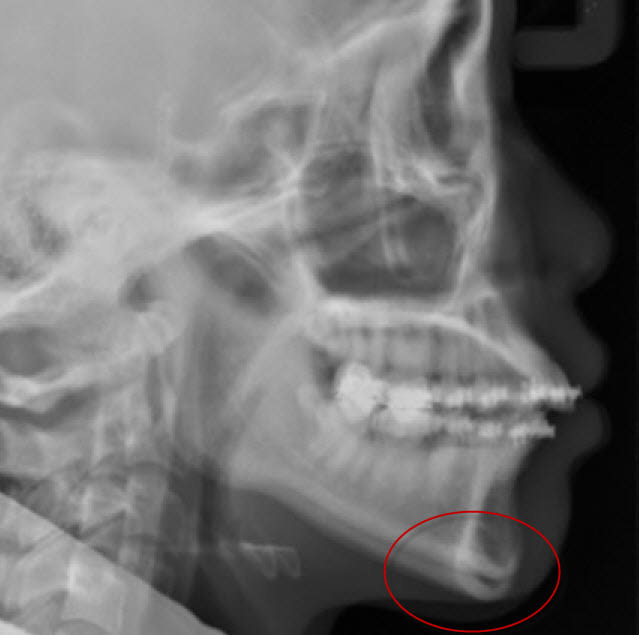

Mon cher Saïd, la superposition que j'ai faite, je l'ai réalisée en prenant la seconde radio, copie, collage comme calque sur la première, superposition sur le maxillaire supérieur et la base du crâne, et en jouant sur la transparence.

La seule chose qu'on constate, c'est une ouverture de l'occlusion, pas un recul mandibulaire. Des points de prématurité, oui, mais pas de recul condylien.

Maintenant, observe bien ci-dessous les clichés avant et après :

Tu constateras que le nivellement orthodontique de Seespan a entraîné une distoversion molaires inférieure.

Cette distoversion molaire a créé cette fameuse classe II dentaire (et non pas squelettique comme le prétend Seespan) et est de facto à l'origine de l'apparition de la béance à cause des prématurités, comme c'est classique.

Seespan prétend qu'il suffira de corriger ces prématurité pour qu'overjet, open bite et tout le reste disparaisse "sans extraction et sans chirurgie", là il se fiche dedans dans les grandes largeurs, son traitement ne sera pas si simple que ça !